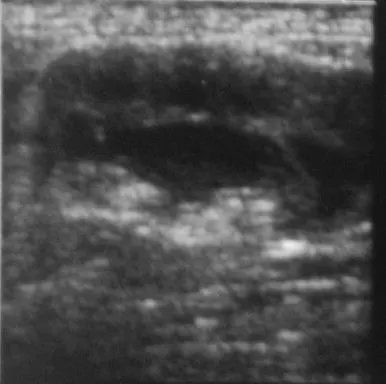

Abdominal ultrasonography (from patient in Figure 2) showing hydronephrosis and necrotic debris in both renal pelvises (A); close-up view of the right kidney (B).